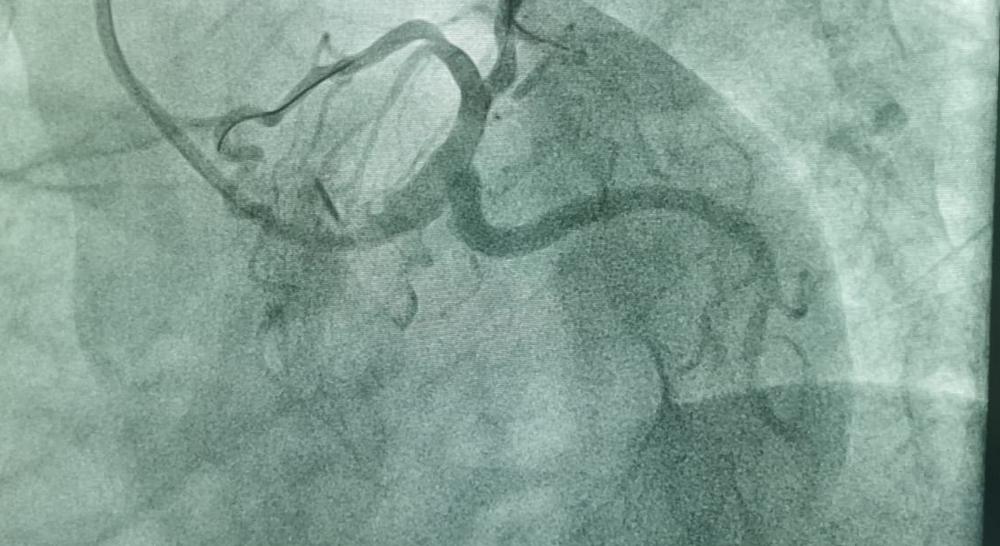

По словам врачей, подобный диагноз опасен для жизни. Риск сердечного приступа у пациента был очень высок. В связи с этим врачи рекомендовали ему стентирование коронарных артерий на республиканском уровне в Нур-Султане или Алматы. Но пациент отказался от этого предложения.

- Тогда актауские врачи пригласили коллегу из столицы для проведения операции в стенах областной больницы. Операция проведена с участием старшего ординатора ангиохирургии, интервенционного врача-кардиолога и интервенционного аритмолога 1 категории областной больницы Курбанали Сабдинова. Операция прошла успешно. После стентирования больной был переведен в палату. На данный момент он выписан домой, - сообщили в центре общественных коммуникаций региона.